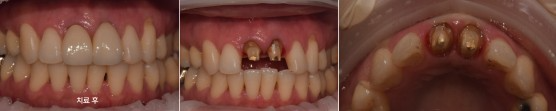

재신경치료 후 보철 치료

#11,21 뿌리 끝에 염증있어서 re-endo후 post cr설명 드리고 진행함.

치료 전

치료 후